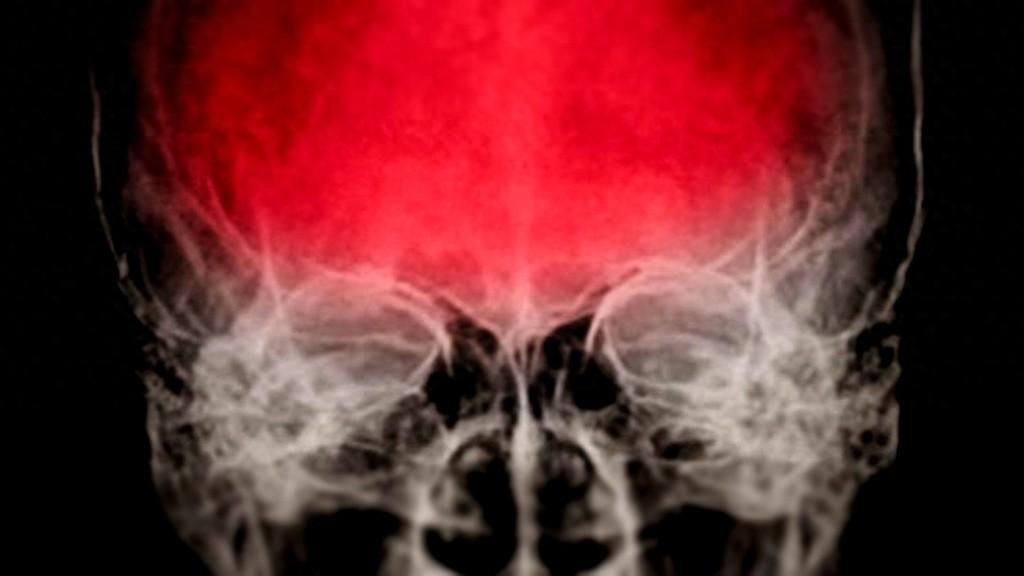

這個有點恐怖,一項最新研究發現,我們大腦里居然潛藏着很多病毒,就像潛伏的定時炸彈一樣,隨時可能被激活,引發一系列神經退行性疾病,最嚴重的可能是阿爾茨海默病——我們常說的癡呆症。這項研究已發表在1月7日《科學-信號》雜誌上。

但我們也不能完全不擔心,因爲它們一旦遇到適當的條件,比如免疫系統變弱或外部刺激,就有可能被激活,開始“搗亂”。這項研究表明,腦震盪等頭部創傷可能是讓這些病毒“醒來”的催化劑,進而引發一系列神經退行性變化。

當模擬頭部創傷(類似腦震盪)時,研究人員發現,潛伏在模型中的HSV-1病毒被激活,開始引發一系列阿爾茨海默病的特徵,如澱粉樣斑塊、tau蛋白纏結、神經元死亡等。

這些標誌性的變化與我們通常在患有阿爾茨海默病的患者大腦中看到的病理特徵驚人地相似。這一發現引發了一個新的問題:是不是腦震盪會激活這些潛伏病毒,從而加速阿爾茨海默病的發展?